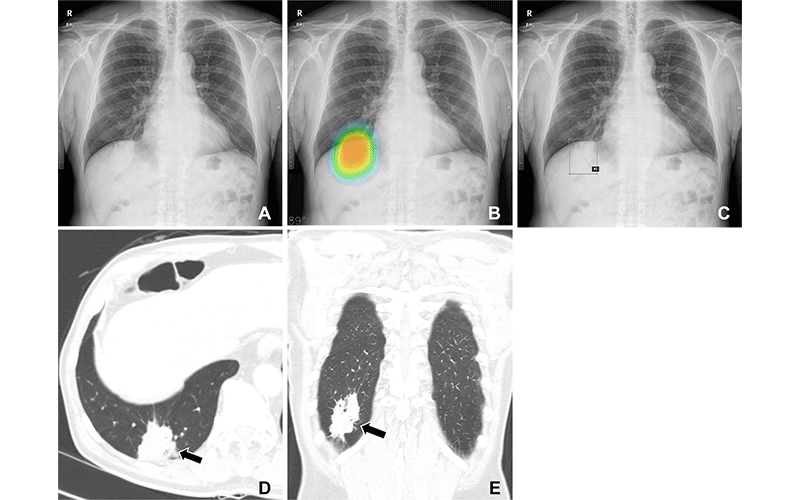

Lung cancer detection in above figures

4. CT Scans: Detailed Cross-Sectional Imaging

CT (Computed Tomography) scans use X-rays to create detailed cross-sectional images of the body. They are widely used to detect and stage cancers in the lungs, liver, pancreas, and brain. CT scans help determine the exact size and spread of tumors.